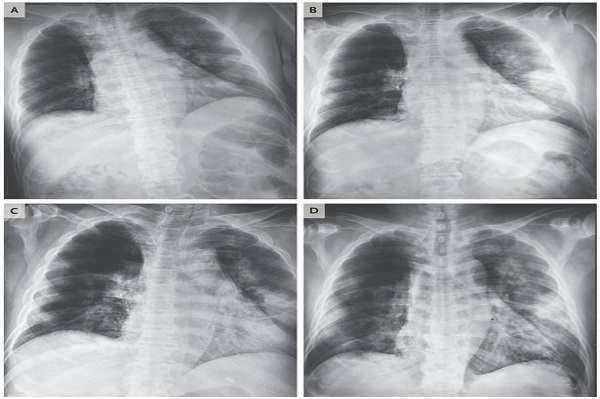

| Foto paru-paru pria Vietnam yang terinfeksi COVID-19. Foto/RSNA |

Ada juga seorang wanita berusia 45 tahun dari Provinsi Sichuan, China, didiagnosis terinfeksi COVID-19 setelah kembali dari Jepang dan menderita demam, batuk, dan nyeri dada. Menurut jurnal medis Radiology, ada bercak putih yang meluas ketika dilakukan pemindaian dada dan terdapat "tanda halo terbalik" terlihat di lobus kiri atas.

Di Amerika Serikat (AS), dokter-dokter di Rumah Sakit Mount Sinai di New York City adalah yang pertama di Amerika yang menganalisis CT scan penderita COVID-19. Para dokter mengatakan mereka mengidentifikasi pola khusus pada paru-paru dari puluhan pasien yang dirawat di rumah sakit di China pada puncak epidemi di sana.

Ground glass opacity menjadi lebih padat dari waktu ke waktu, dan polanya mirip dengan yang ditemukan pada pasien yang terpapar SARS atau pun MERS.